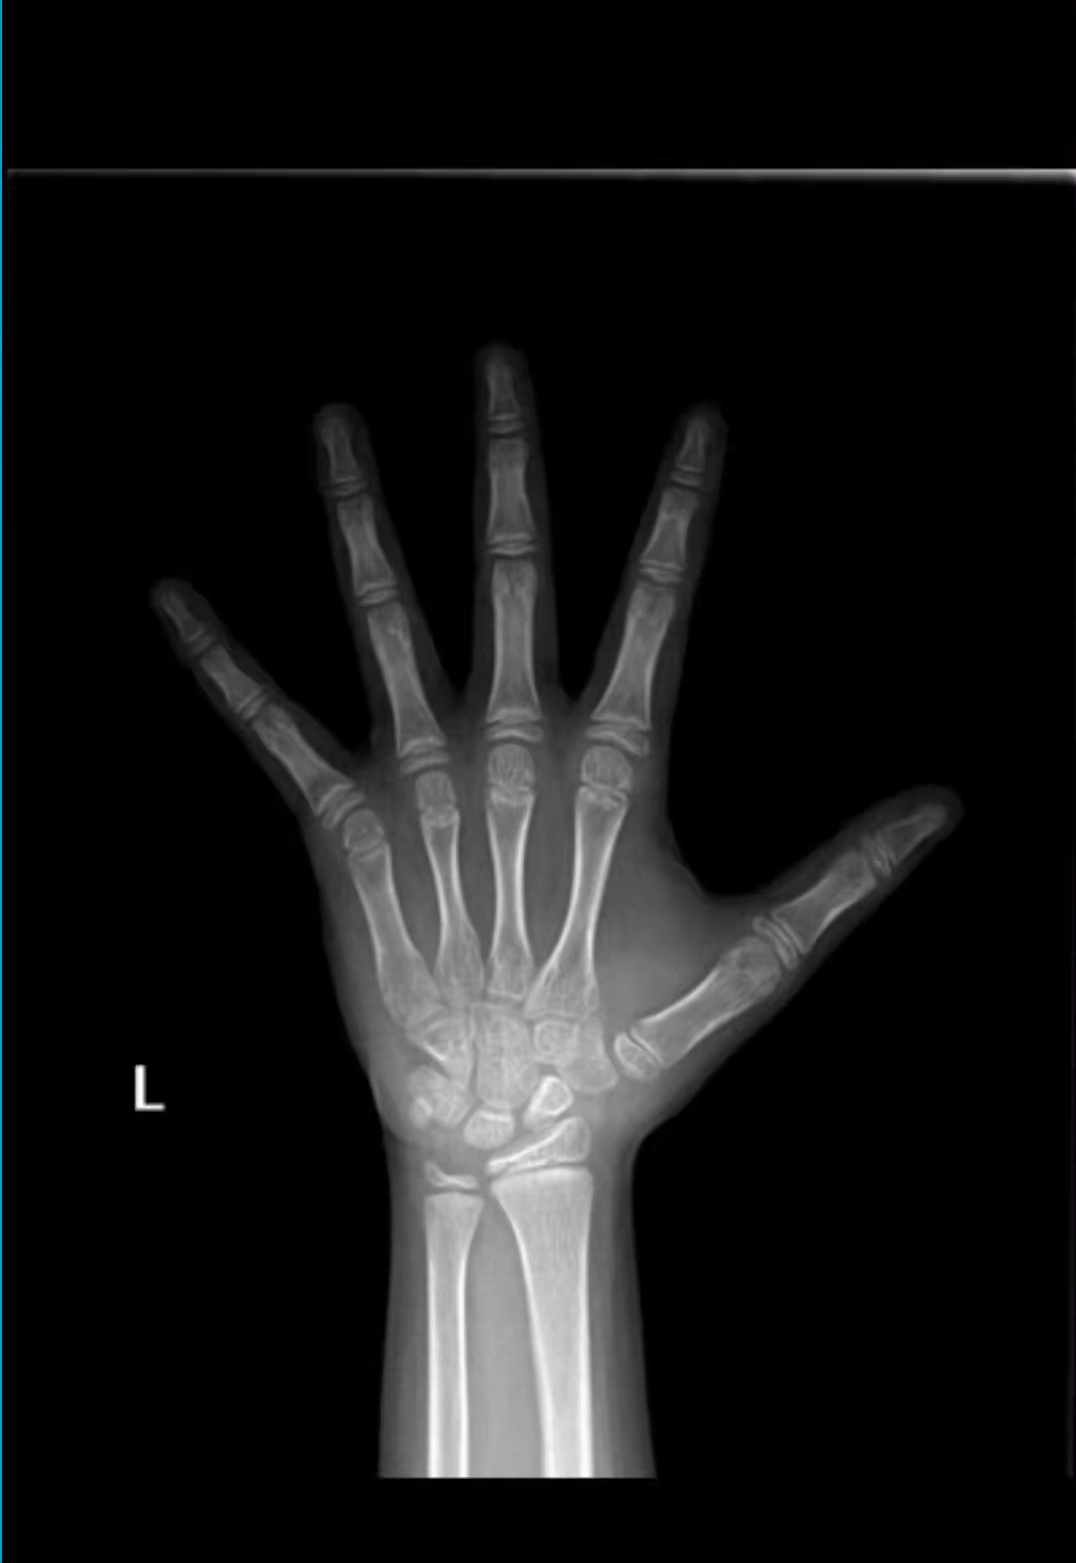

第一步,拍骨龄片

我建议处于生长发育期的孩子,可以定期拍摄骨龄片,结合此身高表,预估孩子的成长空间。尤其是遗传身高不理想,身高过矮、身高超高,以及肥胖的儿童,更需要重点监测骨龄。

哪里可以拍骨龄片?建议去专业的生长发育门诊,或者小儿内分泌科拍摄;如果当地医院没有这两个科室,一般能拍x光的医院都可以拍骨龄片,但是医生可能不会评估骨龄片;可以将骨龄片后台留言给我,我帮家长评估。